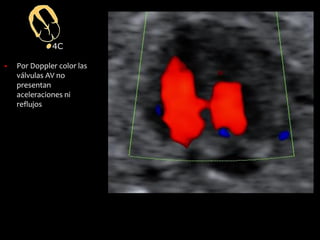

▪ Por Doppler color las

válvulas AV no

presentan

aceleraciones ni

reflujos